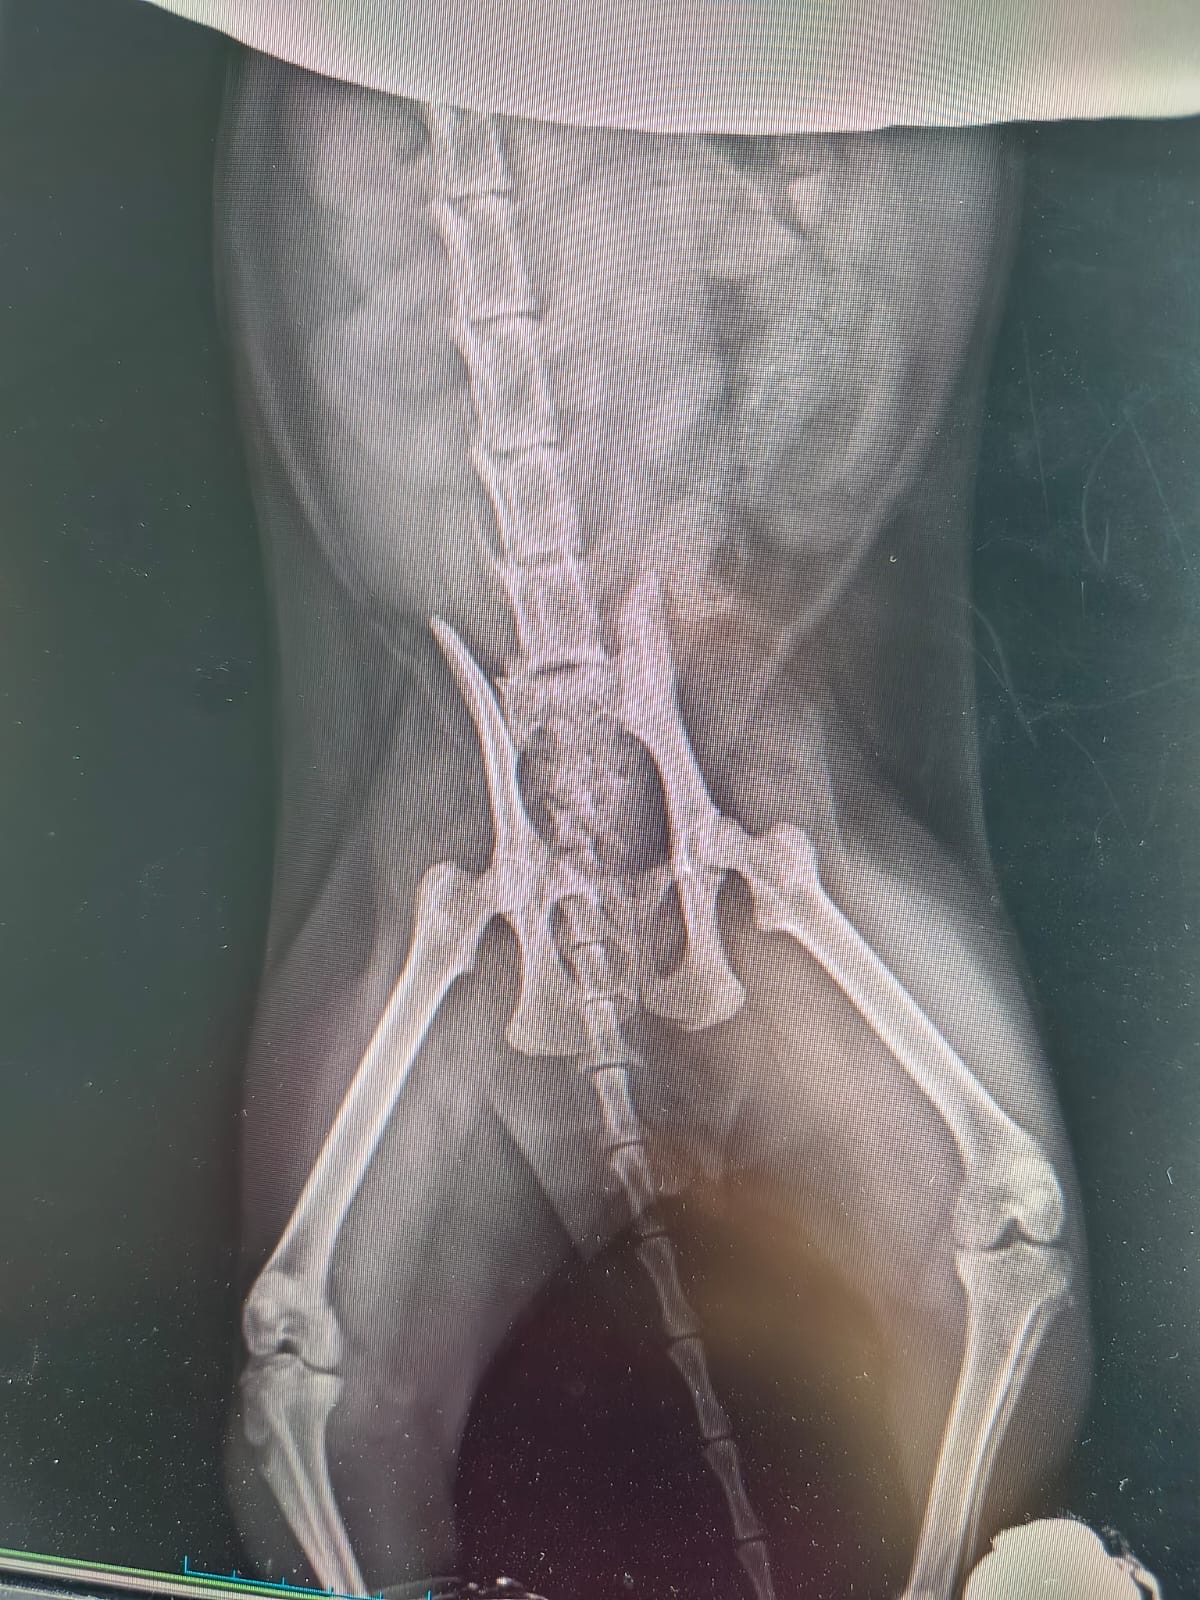

Ha una gravissima lesione alla colonna vertebrale, tra la quinta e la sesta vertebra.

- Esami specialistici (TAC, lastre, visite)